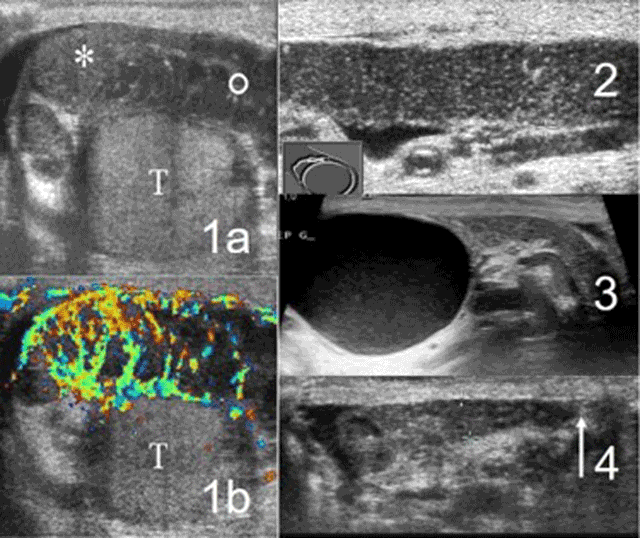

Figure 3

Excretory tube analysis: typical acute epididymitis (1a, 1b), dilatation of the epididymal body (2), cyst of the epididymal head (3), absence of vas deferens (4).